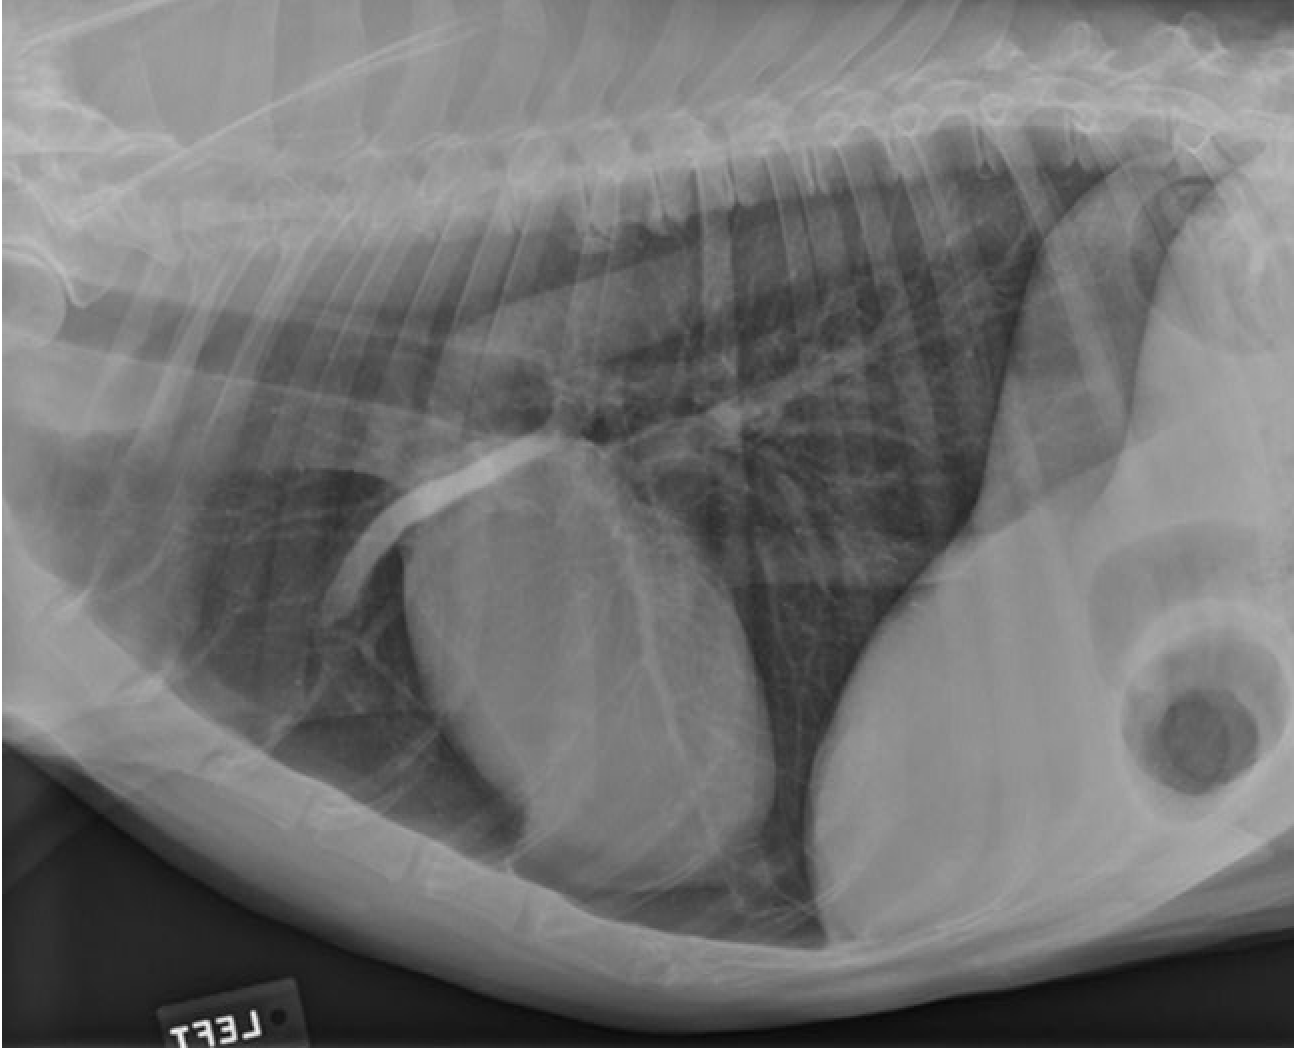

identity the structures on the thorax radiograph left lateral view

heart

identify the right cranial pulmonary vein

identify the pulmonary arteries

identify the right cranial lung lobe

identify the right cranial bronchus

identify the right accessory lobe of the lung

identify the right crus of the diaphragm

identify the left crus of the diaphragm

identify the dome of the diaphgram

identify the left cranial lung lobe